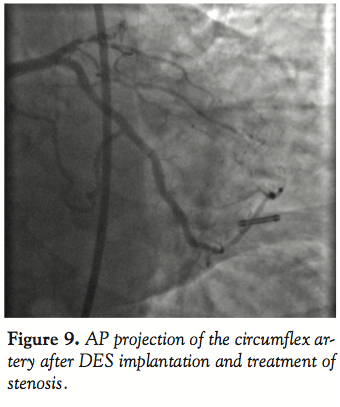

Case 3. A 65-year-old male presented with unstable angina. Diagnostic angiography demonstrated triple vessel coronary disease and normal ventricular function (Figure 7). After intervention on the RCA was performed, attention was turned to the circumflex artery (Figure 8). A 7 Fr EBU (Medtronic Vascular) guiding catheter was used for the intervention on the circumflex artery. A BMW (Abbott Vascular) guidewire was used to cross the lesion in the circumflex artery and angioplasty performed with a 3mm Voyager (Abbott Vascular) balloon. After

predilatation, there was difficulty advancing the stents through the calcified proximal vessel (Figure 8). A GuideLiner catheter was then advanced into the circumflex artery and this facilitated delivery of long drug-eluting stents to treat the stenosis successfully without need for a different wire or a different guiding catheter (Figure 9).

In the third, fourth, and fifth cases, the reason for the development of this device, facilitating distal stent delivery, is demonstrated. Commonly used methods to overcome difficulty with stent delivery include straightening of the vessel with a buddy wire, use of an anchor balloon, and using large diameter guiding catheters with more supportive curves. The GuideLiner facilitates delivery of stents to distal segments of the coronary vessel (Figures 4 and 5) by allowing safe deep vessel intubation. This provides the necessary extra back-up support needed for stent delivery. In an era when radial artery intervention is making a comeback into the mainstream, this may have added significance because the vast majority of cases via the radial artery are performed with 6 Fr guiding catheters. Also because of the angle of entry from the radial approach into the aortic sinus, coaxial guide placement is difficult. The GuideLiner catheter may allow for maintaining coaxial guide orientation. In case 3, a long circumflex artery stenosis was treated with deep engagement of the GuideLiner catheter to deliver 2 long DES as opposed to several shorter length drug-eluting stents. This may have incremental value in an era of cost containment by treating long lesions with fewer drug-eluting stents, thus lowering the cost per case.